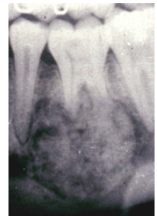

What is the radiological appearance of a Cementoblastoma?

Radiopaque Lesion attached to Tooth Root with a Radiolucent Margin

What is the Histological Appearance of a Cementoblastoma?

Sheets of Cementum and Osteoid in a Mosaic Pattern, many plump Cementoblasts

- Resemble Osteoblastoma